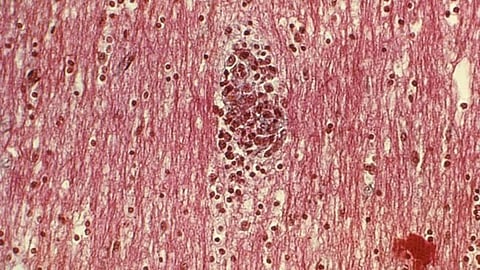

They concluded that none of these engulfed microglial debris. Instead, they found that it is the astrocytes that do the job. These are a type of glial cell, those non-neuronal cells in the nervous system that perform support work for the neurons.

The normal job of the star-shaped astrocyte glial cells is manifold: nutrient provision to nervous tissue, regulation of blood flow in the brain, and repair and scarring after infection or injury, amongst other tasks. But astrocytes are not normally involved in microglial work of clearing away cellular debris. This is ‘part-time’ work, taking over from the normal janitors.